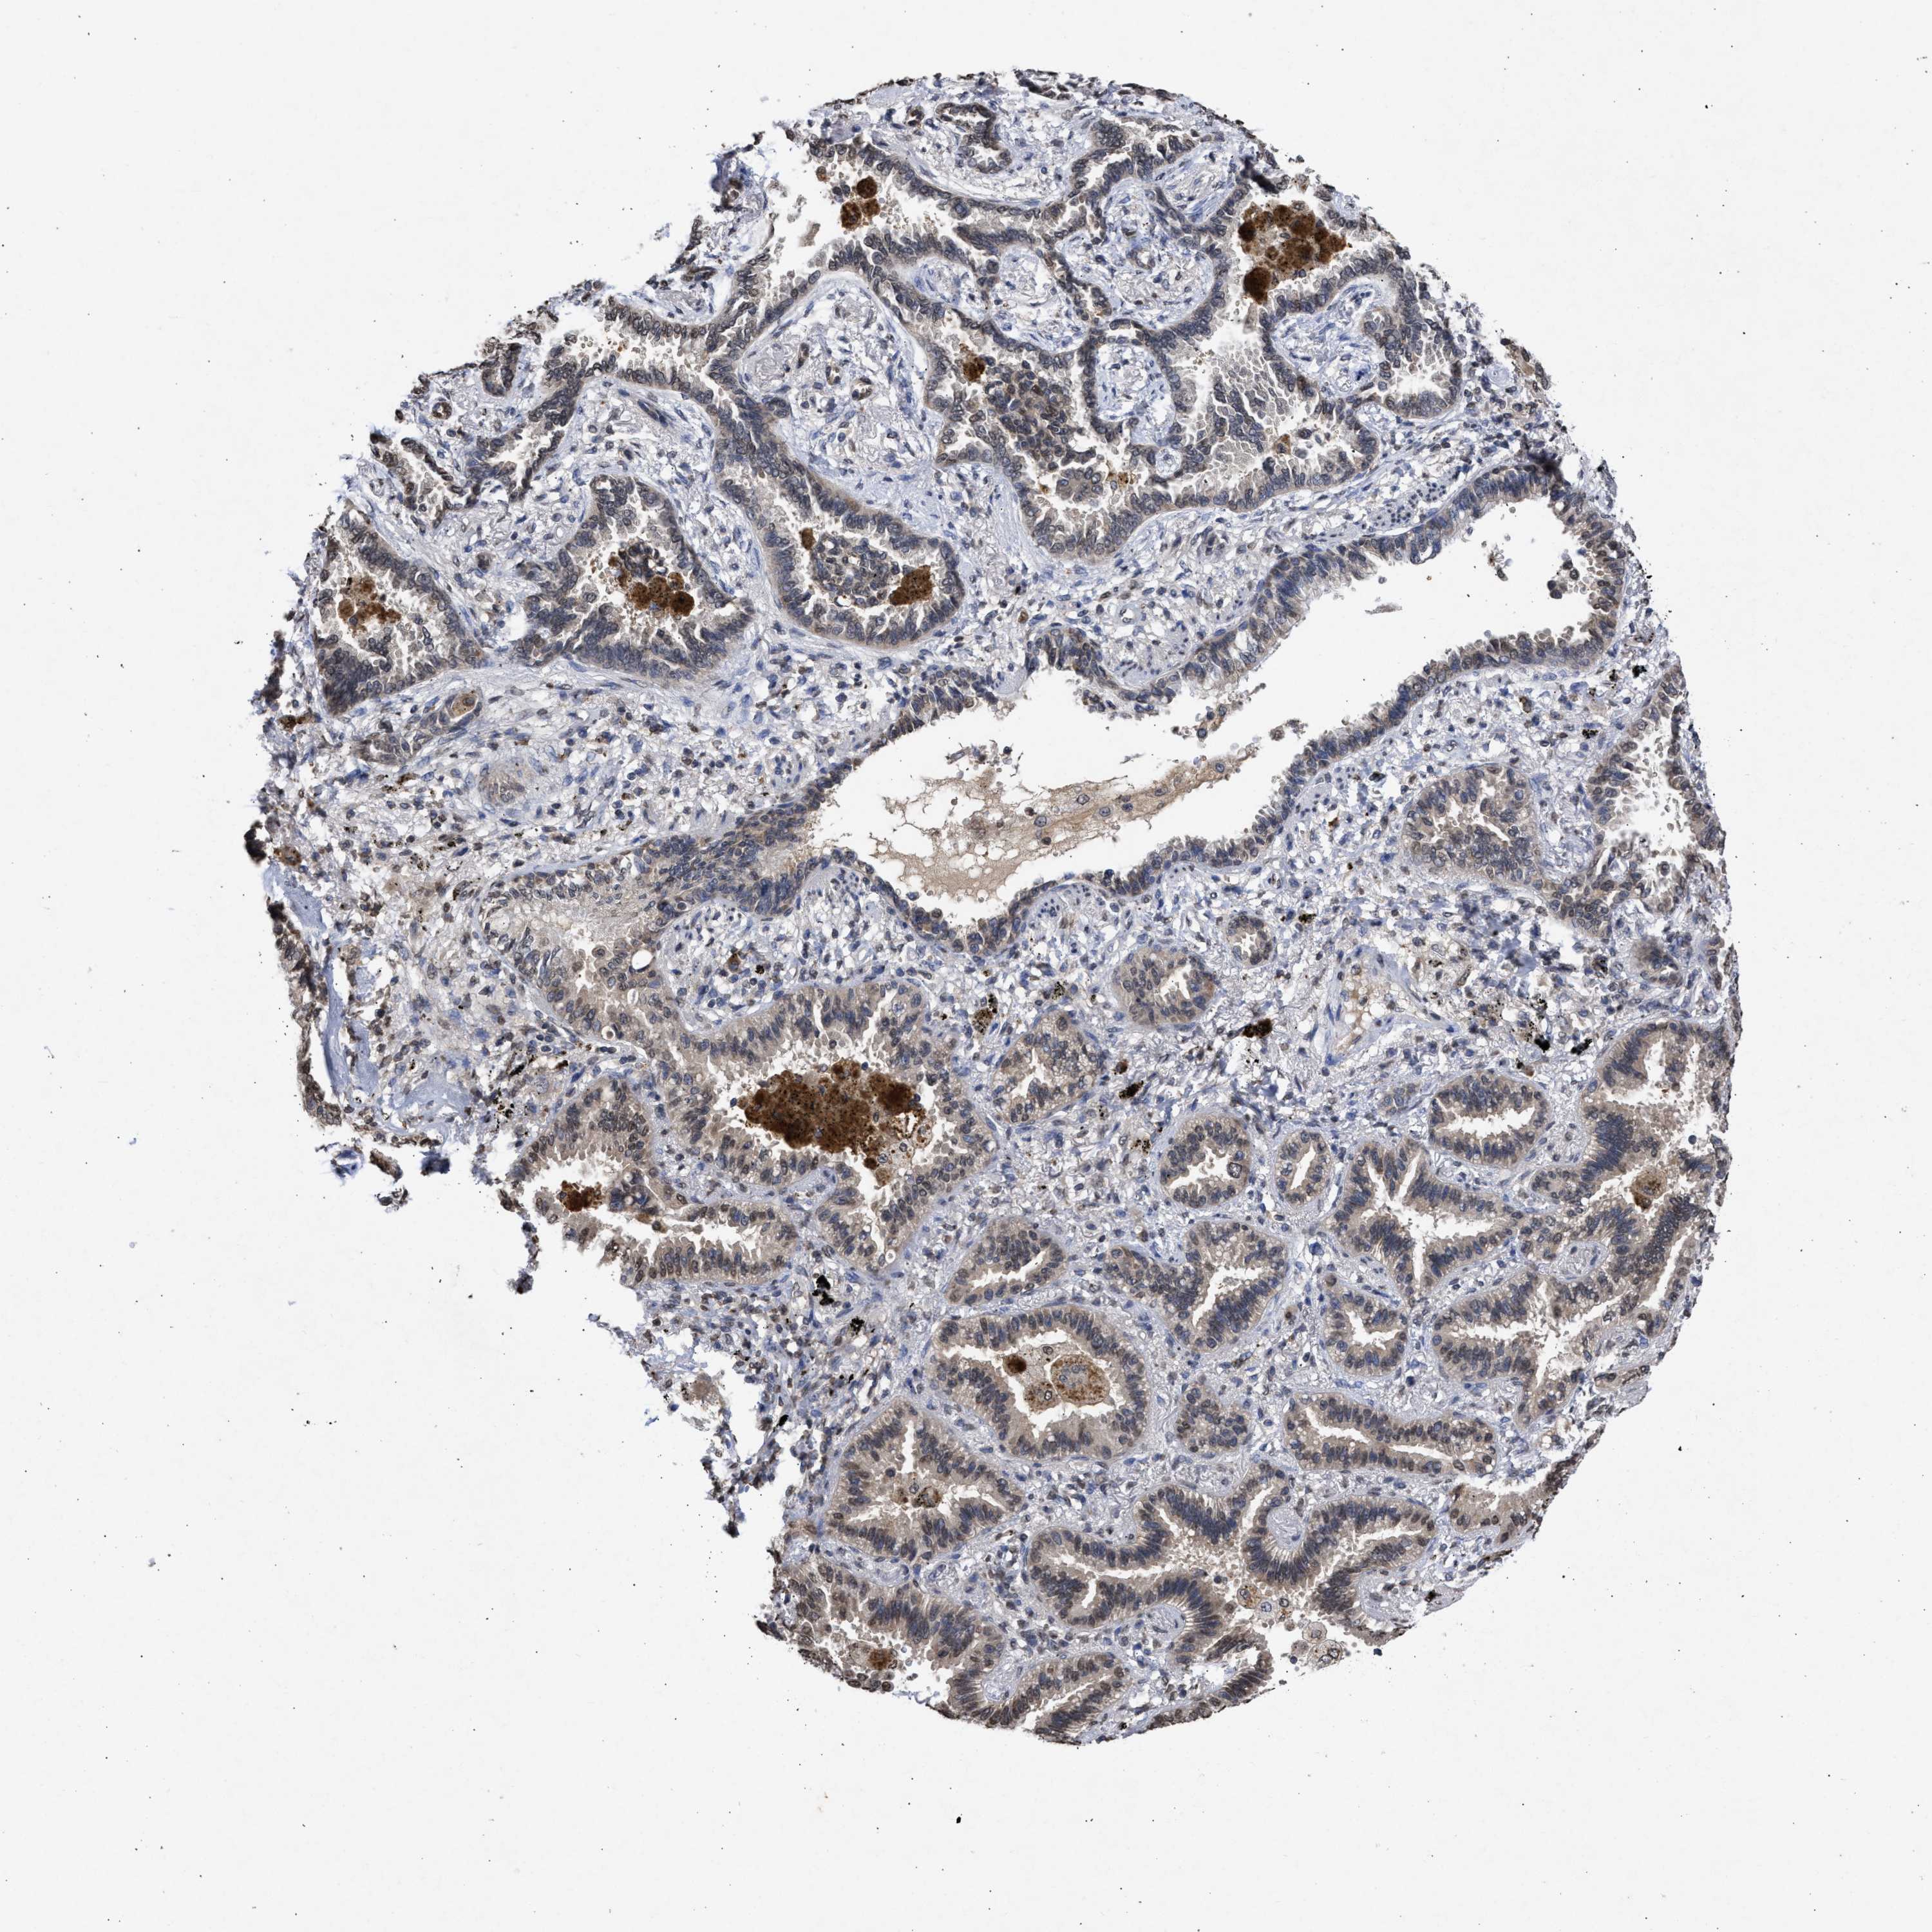

CANCER LUNG CANCER Show tissue menu

Lung cancer

Human cancer

Lung adenocarcinoma

Lung squamous cell carcinoma